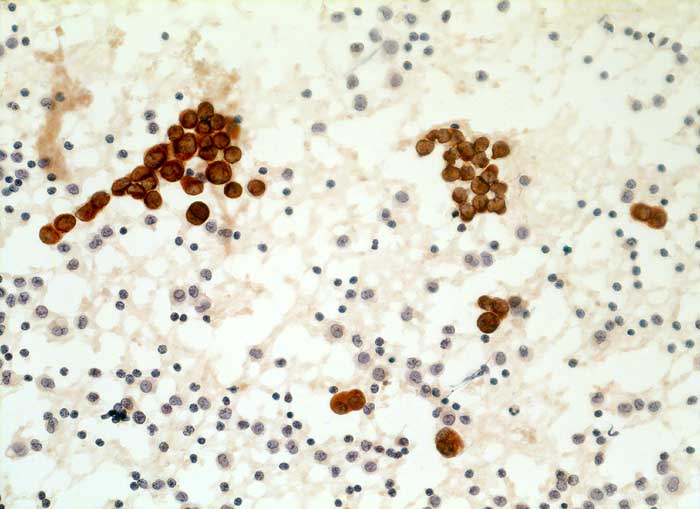

CK22 und Lu-5 repräsentieren Zytokeratingemische, welche einen Grossteil normaler und neoplastischer Epithelzellen anfärben.

Reaktion in Neoplasien:

Die meisten Karzinome und vereinzelte Sarkome reagieren positiv mit diesen Panzytokeratinen. CK22 ist etwas sensitiver und spezifischer als Lu-5. Entdifferenzierte oder sarkomatoide Karzinome können die Positivität für Zytokeratine verlieren.